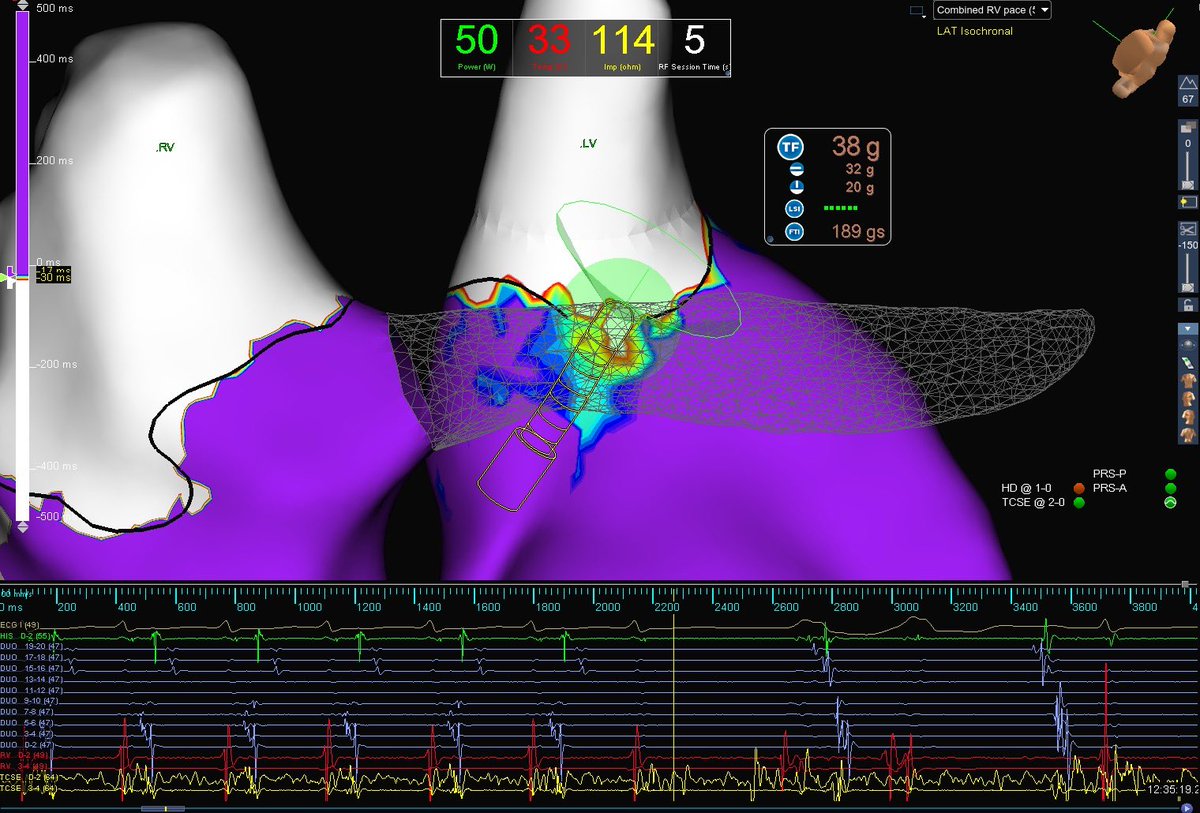

Fidelity of HD grid signals is impressive. Here is a TAPVR (repair: baffle to single RSPV) patient with both fib and flutter. After PVI rhythm organized to flutter, the entire CL on the grid on lat MA. Termination during ablation! Thanks to mapping help @sarahwhittam11